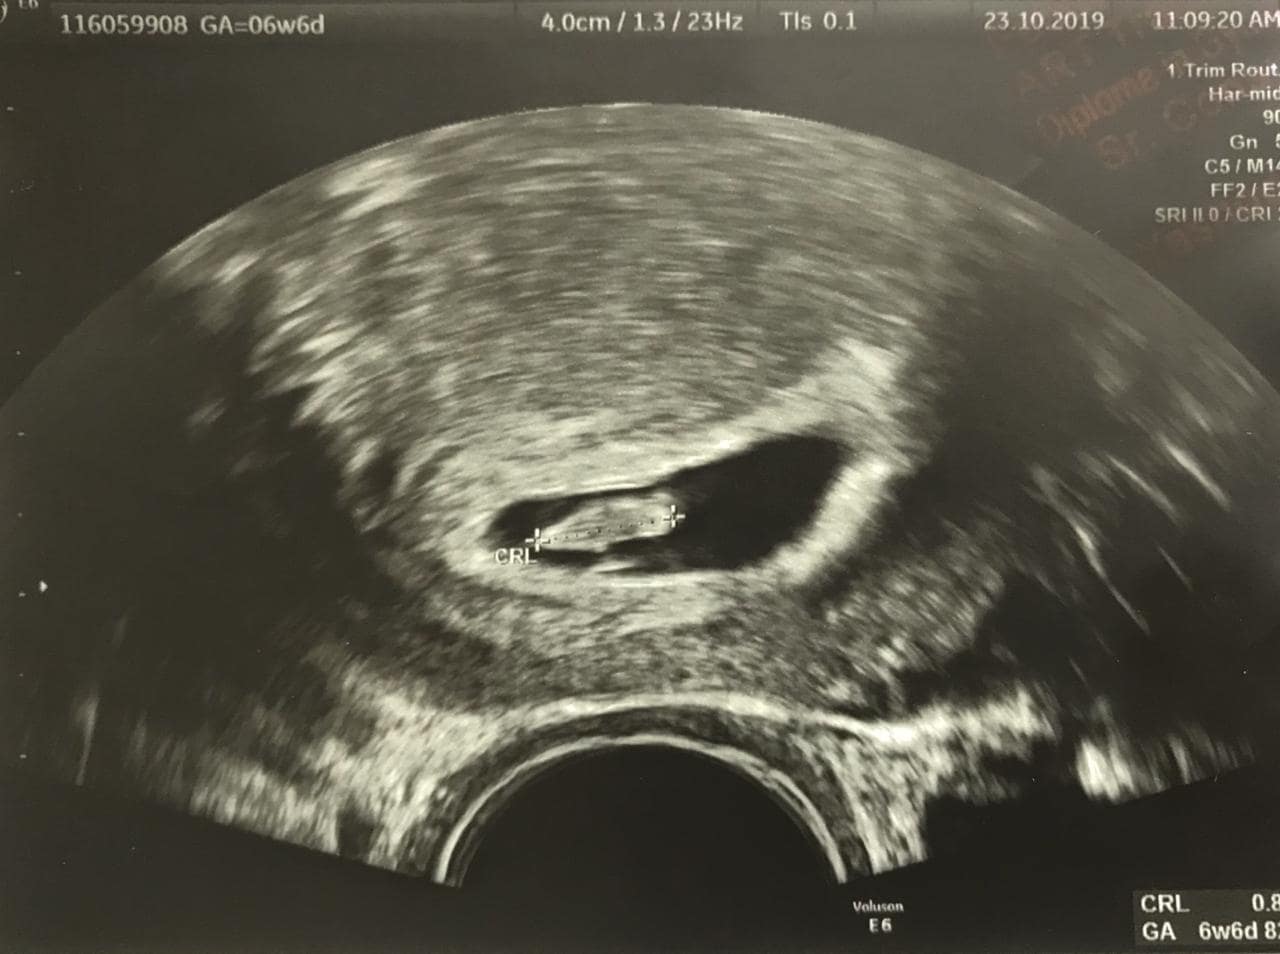

The patient was very keen on trying IVF with self-eggs again and did not want to go for donor eggs. She was put on Folic acid, antioxidants, and multivitamins for 3 months to improve her egg quality and response to treatment. IVF was done here with Recombinant gonadotropins. We managed to get 6 oocytes out of which we got 3 good embryos, which were frozen. The endometriosis was then treated with a GnRH Agonist suppression therapy followed by a frozen thawed embryo transfer. SBHCG 2 weeks after transfer was 463.7 mIU/ml. The latest scan showed a single live foetus with cardiac activity and a CRL of 0.8cm corresponding to 6 weeks 6 days of pregnancy.